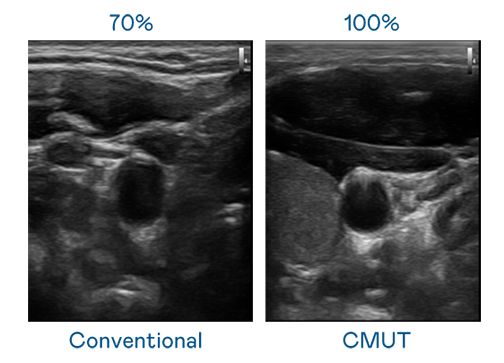

CMUT 技术是一种用电容式微机电元件来产生超音波讯号的技术。与传统 PZT 压电式技术相比,CMUT 频宽增加 30%,更宽频的超音波讯号让影像解析度大幅提升,是实现高影像品质医疗超音波扫描、促进精准医疗发展的关键技术。

超音波影像的解析度高低,首先取决于探头能发出的讯号频宽。人生就是博·z6尊龙 CMUT 可提供高清晰的超音波讯号,提供高频宽、高灵敏度、影像纹理细节更高的超音波影像,协助医护人员缩短影像判读时间及利用精准的医疗影像进行诊断。